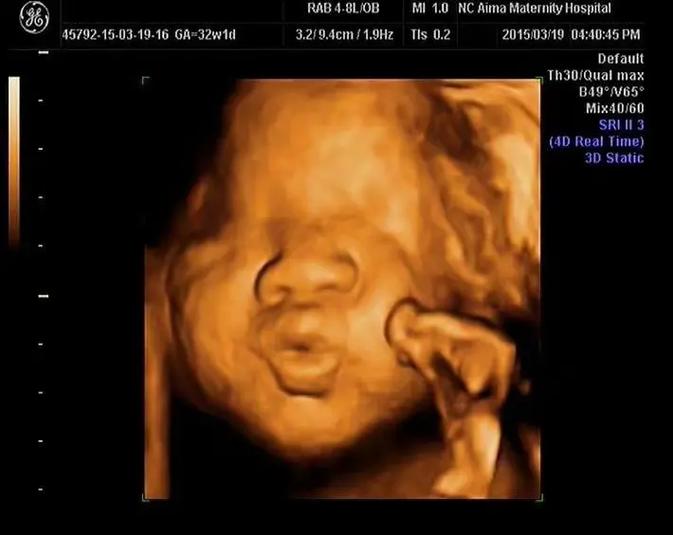

在胚胎移植成功后,我们迎来了四维彩超检查。这是一种先进的超声技术,可以清晰地显示胎儿的立体图像。四维彩超不仅可以检查胎儿的生长发育情况,还能排查一些先天性疾病。

检查当天,我怀着既紧张又兴奋的心情来到了医院。医生让我躺在检查床上,然后在我肚子上涂抹了一些凝胶。随后,医生用一个探头在我的肚子上轻轻滑动,屏幕上便出现了宝宝的立体图像。

四维彩超最大的意义在于,它让我们提前见到了宝宝的样子,也让我们更加真切地感受到了宝宝的存在。看着屏幕上的宝宝,我不禁热泪盈眶。同时,四维彩超也为医生提供了重要的诊断信息,有助于评估宝宝的健康状况。

经过仔细检查,医生告诉我们,宝宝的发育一切正常,没有发现任何异常。这个结果让我们悬着的心终于放下了。我们感激涕零,感谢医生,感谢科技,更感谢这个小生命的到来。